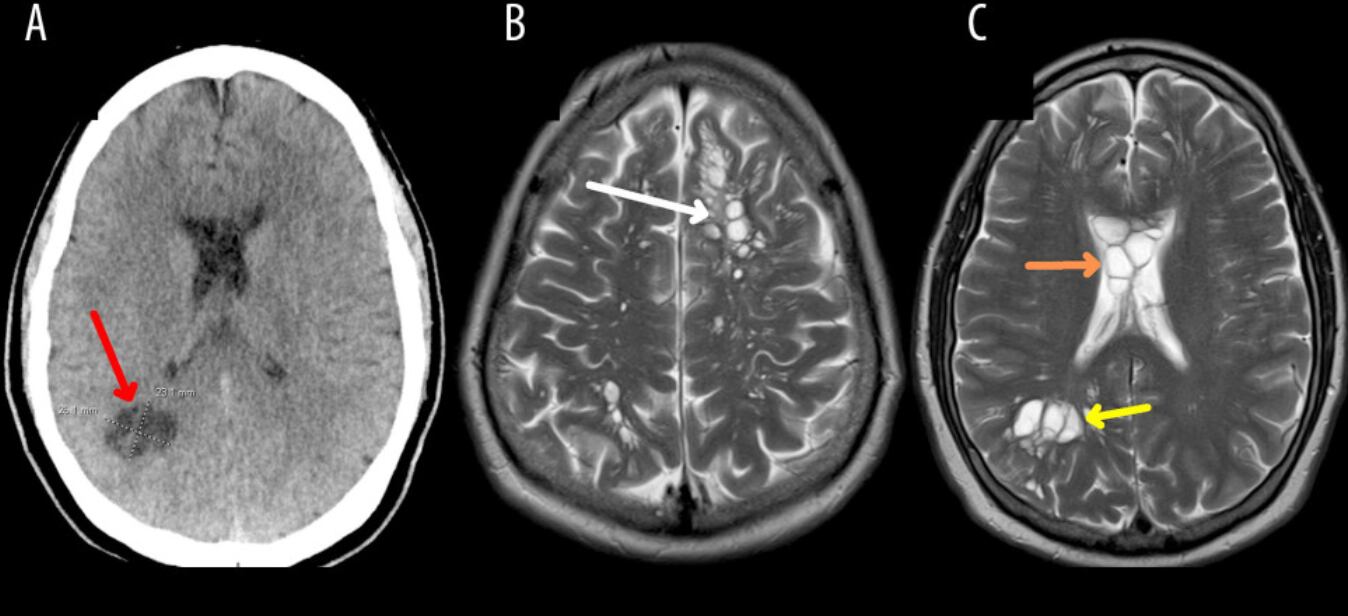

Según el reporte de CNN, el médico le hizo una tomografía que reveló múltiples quistes en todo el cerebro. Ante la sospecha inicial de que pudiera padecer una enfermedad neurológica extraña denominada quistes neurogliales congénitos, los médicos le ingresaron en un hospital de Orlando para consultar con neurocirugía.

Y bueno, los exámenes que ahí le practicaron, arrojaron que los quistes eran larvas, que se instalaron en el cerebro y le causaron una infección denominada neurocisticercosis.